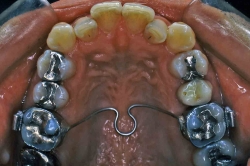

パラータルバー または パラータルアーチ

構造

歯に付けたリング状の薄い金属板(バンド)と金属ワイヤーで出来ています。患者様の歯形をお取りして、石膏模型の上で予め製作したものを取り付けます。

装置使用の目的

歯並び全体の横幅を維持するために用いる装置です。奥歯が手前に倒れてこないように、固定源を強化するために用いるときもあります(加強固定と言います)。最も幅の維持が必要な位置に取り付けますので、装置の固定されている位置や形態はいろいろですが、装置の基本構造は同じで、写真のように上顎の裏側の形に合わせて少し太めの針金(0.8-1.2mmくらい)を沿わせ、奥歯に固定したバンドと一緒に一体化させて留めてあります。患者さんが自分で取り外すことはできませんが、調節が必要なときは先生が外して、調整後また留め直すという操作を繰り返していきます。